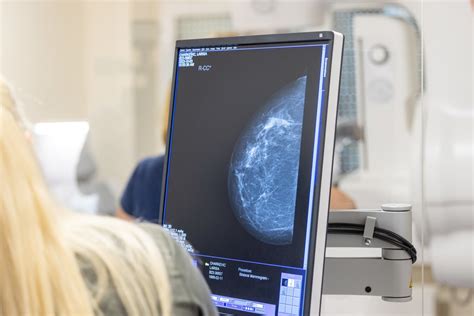

Diagnostikos metodai nėštumo metu

Krūtyje apčiuopiamas kietas, neskausmingas darinys (90 proc. atvejų jį apčiuopia pačios pacientės). Retais atvejais pasirodo kraujingų išskyrų iš spenelio. Metastazavusio vėžio klinika priklauso nuo metastazių vietos. Palpacija išlieka vienu iš ankstyvosios diagnostikos metodų, tačiau dėl nėštumo sukeltų krūties audinio pokyčių jos nauda nedidelė. Tolesni diagnostikos bei gydymo veiksmai nėštumo metu aptariami su įvairių specialistų komanda: onkologu, chirurgu ir akušeriu-ginekologu.

Ultragarsinis krūtų tyrimas padeda atskirti cistinius bei solidžius darinius ir įvertinti sritinius limfmazgius. Tyrimas pasižymi didesniu jautrumu ir specifiškumu nėštumo metu, nei mamografija. Radioizotopinis skenavimas nėščioms moterims nerekomenduojamas.

Patologinis (histologinis) tyrimas. Rekomenduojama stulpelinė arba ekscizinė krūties biopsija, sukeliant vietinį skausmo malšinimą. Dėl aktyvios ląstelių proliferacijos tyrimo vertinimas komplikuotas, todėl tyrėją būtina įspėti, kad pacientė nėščia ar žindyvė.

Krūties vėžio stadijos nustatymas. Krūties vėžio stadiją būtina nustatyti įtarus, kad metastazės plinta, ir tuo atveju, jei išplitimas lokalus. Jei yra besimptominis su nėštumu susijęs krūties vėžys, nuodugnus plaučių, kepenų, kaulų ir kt. sistemų tyrimas gali būti atidėtas, nes metastazavimas mažai tikėtinas.